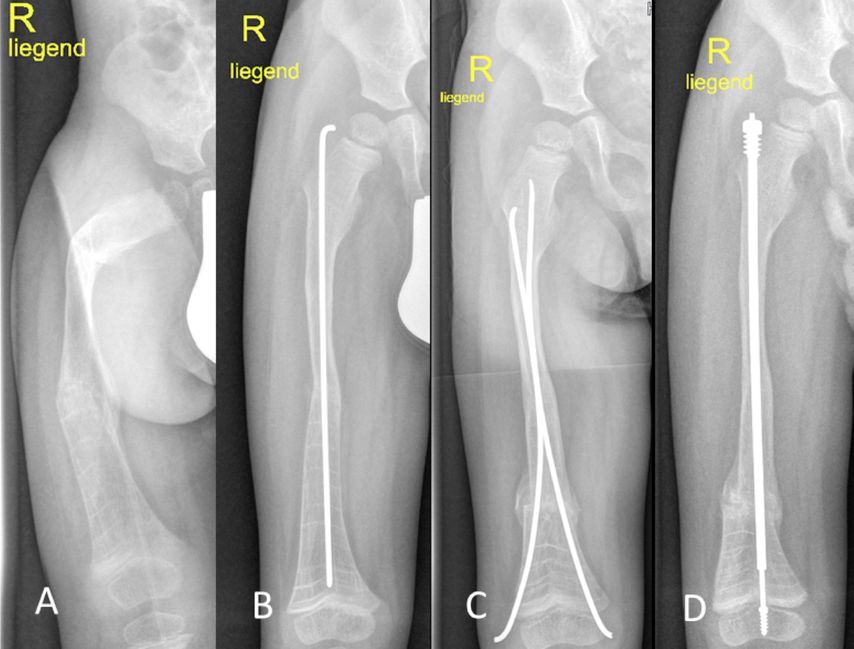

Während bei Kleinkindern aufgrund des geringen intramedullären Durchmessers häufig nur ein Bohrdraht zur Schienung eingebracht wird, können bei größeren Kindern mitwachsende intramedulläre Nägel verwendet werden (Teleskopnagel, wie zum Beispiel Fassier-Duval-Nagel, Abb. 1). Diese ermöglichen eine langstreckige Stabilisierung von der proximalen zur distalen Tibiaepiphyse sowie vom Trochanter major bis zur distalen Femurepiphyse. Das Einbringen intramedullärer Implantate kann durch ausgeprägte Deformitäten, kurze Extremitäten und iatrogene Frakturen kompliziert werden. Plattenosteosynthesen sind aufgrund des hohen Risikos für an die Platte angrenzende Frakturen als Alleinversorgung zu vermeiden.

Abb. 1: A) 2 Jahre alter Knabe, OI 3 mit hoher Frakturrate und Procurvatum/Varus/Maltorsionsdeformität Femur rechts, B) Erstkorrektur mit Bohrdraht nach Doppelosteotomie, C) Akutfraktur unfallchirurgisch extern mit retrograden ESINS versorgt, D) geplanter Umstieg von ESINS auf Fassier-Duval-Teleskopnagel mit erneuter Osteotomie im Alter von 4 Jahren